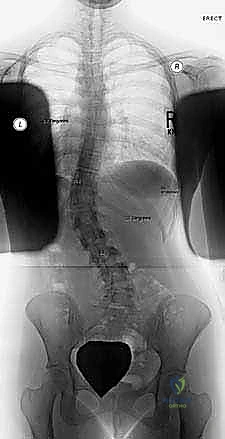

2. التصوير بالأشعة السينية (X-Rays)

هو المعيار الذهبي لتشخيص الجنف. يتم التقاط صور شعاعية لكامل العمود الفقري (من الرقبة إلى الحوض) من الأمام والخلف والجانب، والمريض في وضع الوقوف. من خلال هذه الصور، يقوم الدكتور هطيف بـ:

* قياس زاوية كوب (Cobb Angle): وهي الزاوية التي تحدد شدة الانحناء. الانحناءات الأكبر من 10 درجات تُعتبر جنفاً.

* تقييم النضج العظمي (Risser Sign): من خلال فحص عظام الحوض لمعرفة ما إذا كان المريض لا يزال ينمو، مما يساعد في التنبؤ باحتمالية تدهور الانحناء.